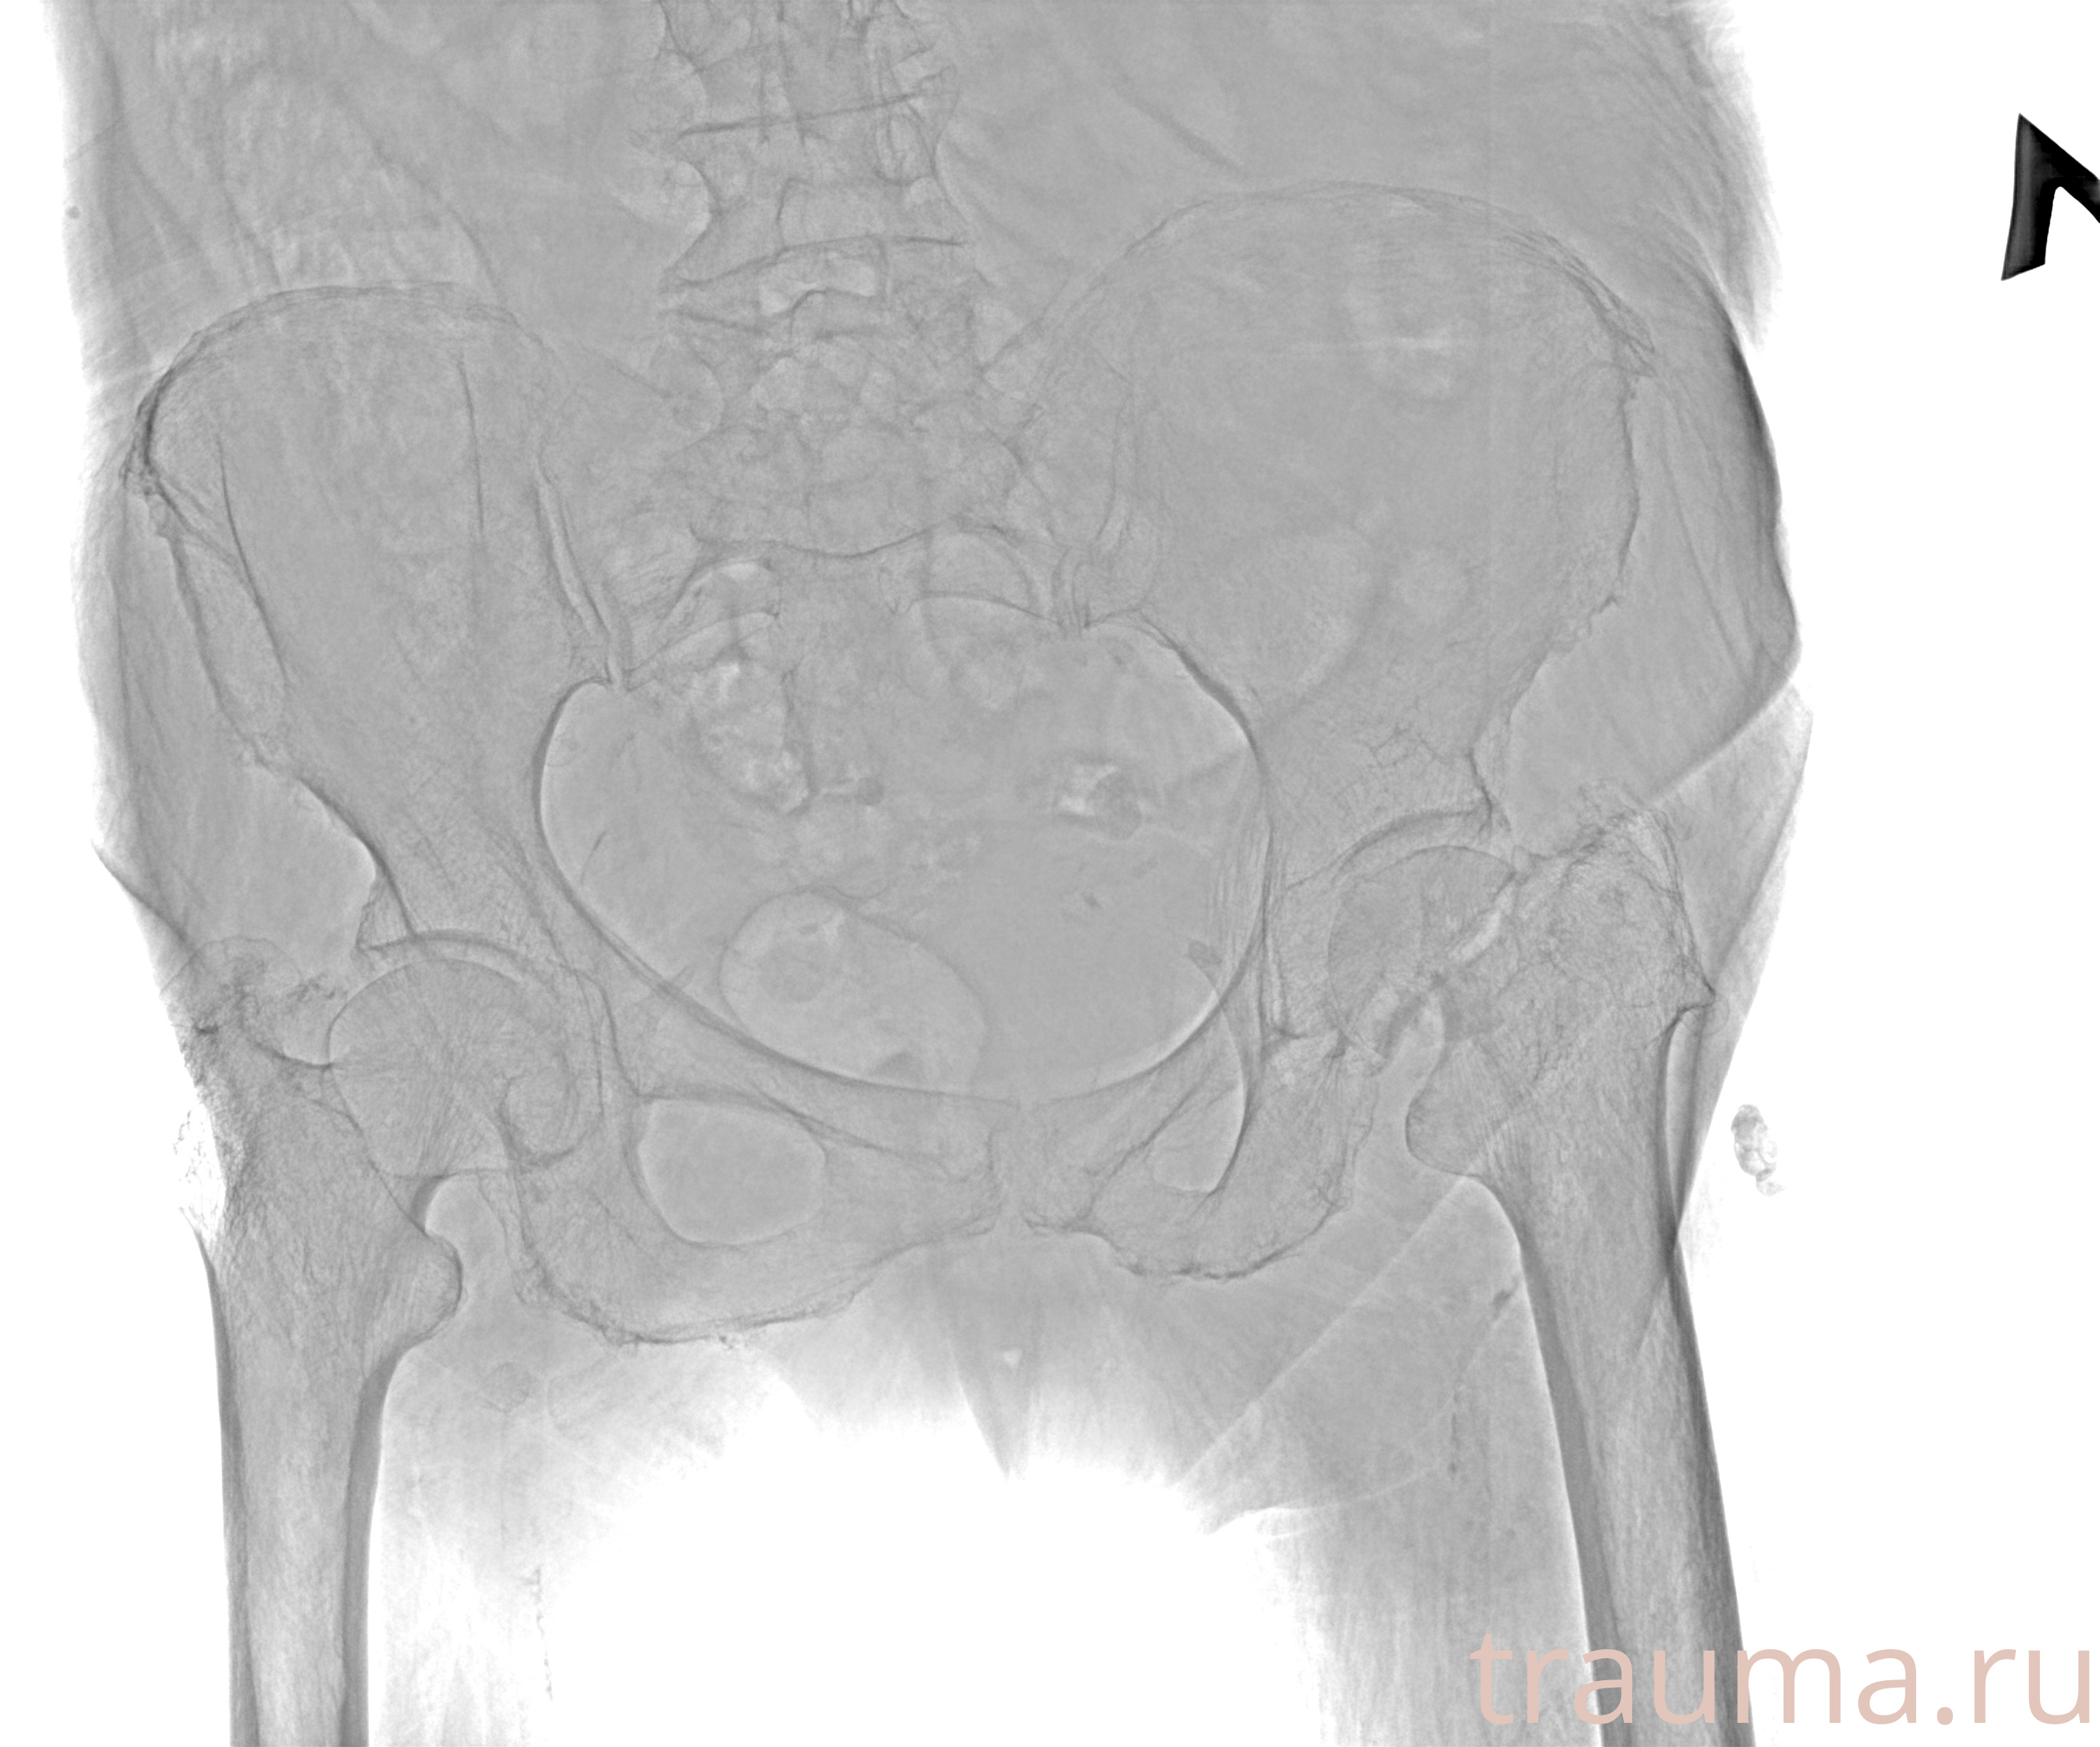

Рентгенограммы

Рентген на дому: по вашему адресу приезжает врач-рентгенолог, травматолог-ортопед с мобильным рентгеновским аппаратом, проводит диагностику травмы или заболевания, делает необходимые рентгенограммы, дает рекомендации по дальнейшему лечению. Получить качественные снимки в домашних условиях возможно благодаря уникальной методике, разработанной МосРентген Центром для института  Склифосовского